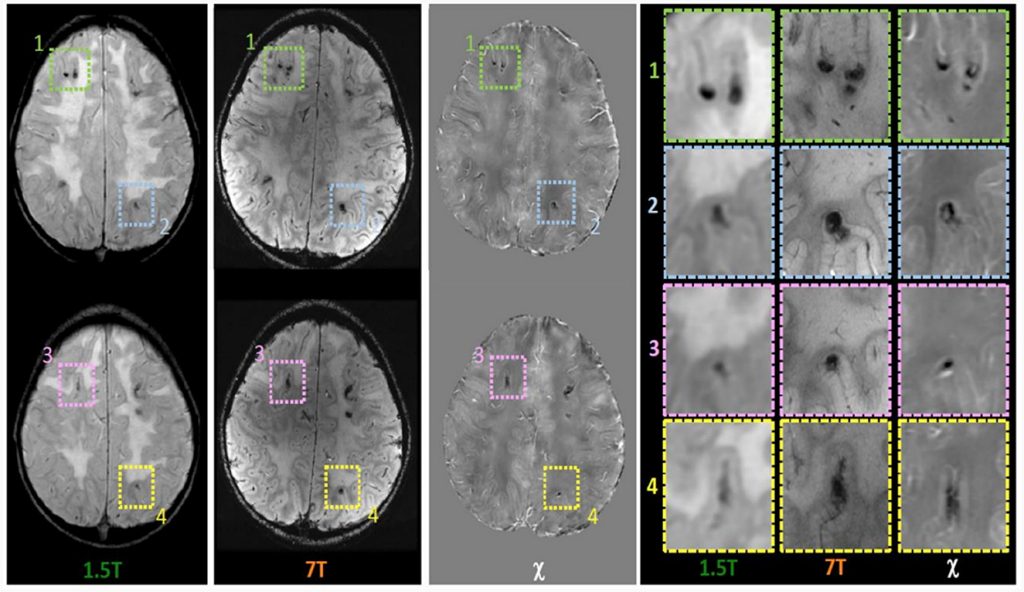

Celardo G, Scaffei E, Buchignani B, Donatelli G, Costagli M, Cristofani P, Canapicchi R, Pasquariello R, Tosetti M, Battini R, Biagi L

Case report: Exploring chemoradiotherapy-induced leukoencephalopathy with 7T imaging and quantitative susceptibility mapping

Frontiers in Neurology, 15: 1362704, 2024

ABSTRACT: Chemotherapy and radiotherapy are widely used in the treatment of central nervous system tumors and acute lymphocytic leukemia even in the pediatric population. However, such treatments run the risk of a broad spectrum of cognitive and neurological deficits. Even though the correlation with cognitive decline is still not clear, neuroradiological defects linked to white matter injury and vasculopathies may be identified. Thanks to the use of 7T MRI it is possible to better define the vascular pattern of the brain lesions with the added advantage of identifying their characteristics and anatomical localization, which, however, are not evident with a conventional brain scan. Moreover, the use of Quantitative Susceptibility Mapping (QSM) makes it possible to discriminate between calcium deposits on vessels (chemo-radiation-induced) and hemoglobin deposition in radio-induced cavernomas, speculating, as a result, about the pathophysiology of iatrogenic brain damage. We describe the case of a 9 year-old boy with a T-type acute lymphoid leukemia who had previously been treated with polychemotherapy and high-dose RT. To better define the child’s neuroradiological pattern, 7T MRI and QSM were performed in addition to conventional imaging examinations. Our case report suggests the potential usefulness of a QSM study to distinguish radio-induced vascular malformations from mineralizing microangiopathy.